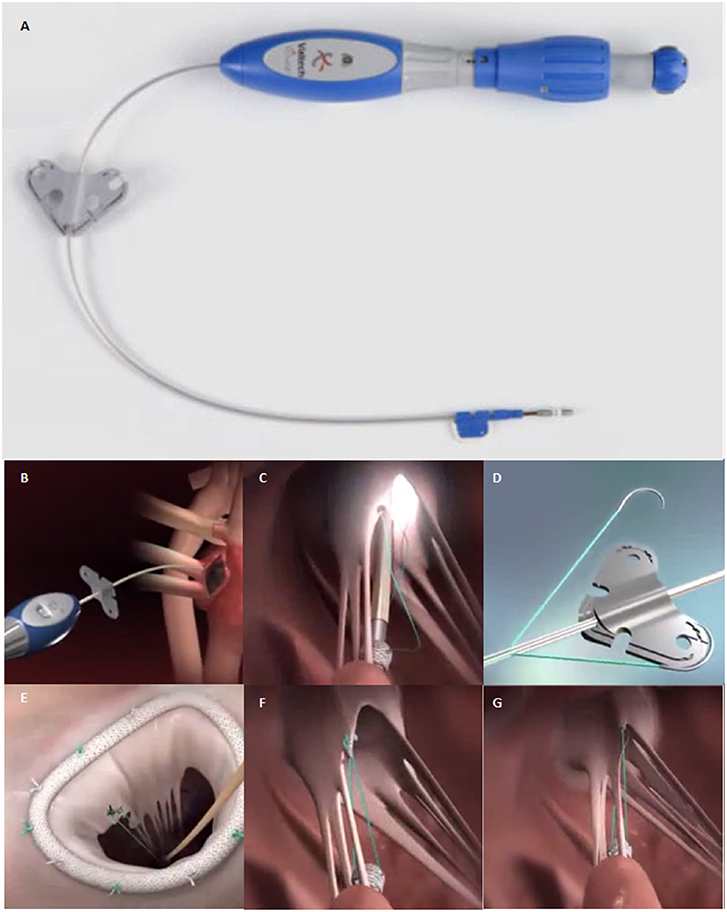

Transcatheter Mitral Valve Chordal Repair: Current Indications And

europepmc.org

europepmc.org

Mitral Valve Repair With A Device For Artificial Chordal Implantation

www.jtcvsopen.org

www.jtcvsopen.org

Frontiers | Transcatheter Mitral Valve Chordal Repair: Current

www.frontiersin.org

www.frontiersin.org

chordal mitral frontiersin perspectives transcatheter indications repair future fcvm

Frontiers | Transcatheter Mitral Valve Chordal Repair: Current

www.frontiersin.org

www.frontiersin.org

mitral transcatheter chordae chordal frontiersin indications perspectives harpoon implantation surgical fcvm

Characteristics Of The Transcatheter Mitral Valve Chord Repair Devices

www.researchgate.net

www.researchgate.net

harpoon mitral chord transcatheter valve tsd edwards devices